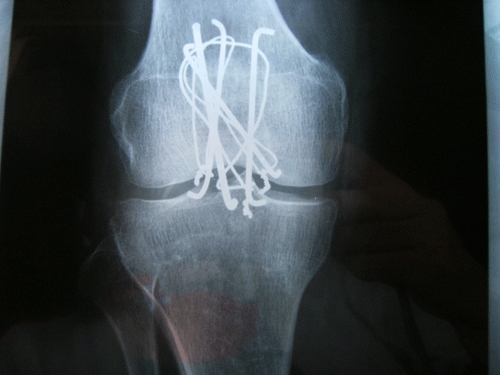

DSCF2041.gif術後25日目。

DSCF2042.gif筑波メディカルセンターへの紹介状を書いて頂く。